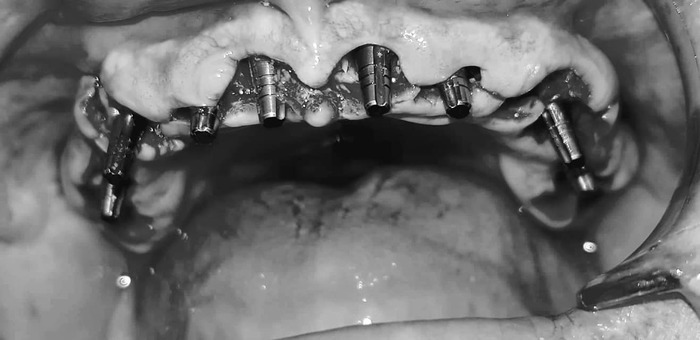

Теперь - как это все дело выглядело в реале:

Вот честно, пока я не увидел именно эти две фотки - я слабо осознавал, какой именно у меня пипец во рту. Каждое утро в зеркале это воспринималось немного не так. Передергивало, конечно, но было привычно. Кстати, все эти фото я увидел уже сильно после лечения и никакого влияния на мое решение лечиться у Георгия они не оказали - не успели )))

А дальше, 3 ноября, за 3 часа времени со мной сделали вот это:

Заметили на последней фотке, какие у меня нижние зубы?